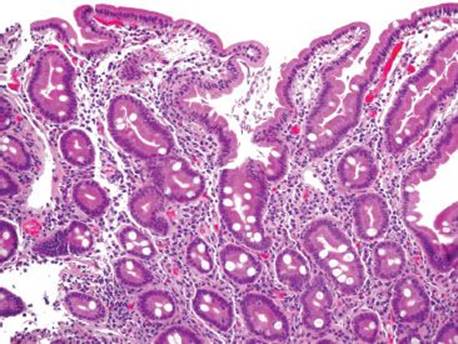

Figure 3.327 Giardiasis. At low power, the duodenal mucosa looks fairly unremarkable, except for the haphazardly arranged luminal debris characteristic of giardiasis. This patient was clinically thought to have an occult malignancy based on the profound weight loss, but all symptoms resolved with Giardiaeradication.

Giardia is the most common intestinal protozoan causing diarrhea in humans (Fig. 3.327).192 Part of the protozoan’s success stems from its ability to infect both the immunocompromised and immunocompetent and its ability to be perpetuated in silent carriers (or asymptomatic patients). This awareness of asymptomatic Giardia infections is important such that one is not misled by a lack of diarrhea&emdash;it happens! Nevertheless, treatment of these asymptomatic cases is critical for prevention of onward spread. The cyst is transmitted via contaminated water or via fecal–oral route, and the flagellated trophozoite adheres to the intestinal epithelium. On duodenal mucosa biopsies, the organisms haphazardly swirl close to the mucosal surface. They can bear such a haphazard arrangement that they can be mistaken for luminal debris to the untrained eye. On closer examination, the trophozoites have been described as clown-faced or pear-shaped based on their peculiar binucleate structure (Figs. 3.328–3.332). Diagnosis can be confirmed with stool smears for the trophozoites or cysts, stool antigen assays, or serologic studies. The only FDA approved treatment is furazolidone (Furoxone),190 although metronidazole is the most common first-line therapy. In the unusual case of recurrent or medically nonresponsive giardiasis, consider the following immunodeficiencies: